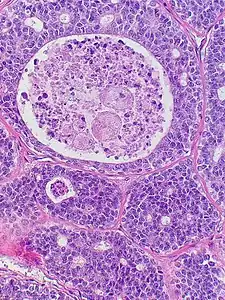

Adenoid cystic carcinoma with comedonecrosis